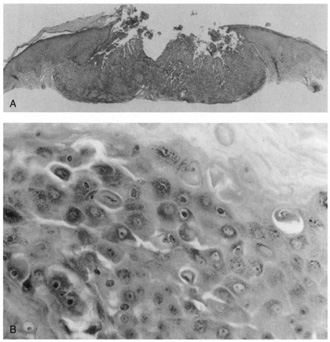

Lesions of molluscum contagiosum often affect the periorbital and lid skin as 1- to 3-mm domeshaped papules with a small central dell. This large pox virus multiplies in the cytoplasm, and, histologically, homogeneous purple intracytoplasmic inclusion bodies (molluscum bodies) are seen in an acanthotic epidermis (see Fig. 7).

Fig. 7. Molluscum Contagiosum—A. Umbilicated lesions typical of molluscum contagiosum on the upper lid of a child. Infection near the edge of the lid may cause a toxic follicular conjunctivitis. B. Low-power photomicrograph demonstrating crater shape of excised lesion (hematoxylin and eosin stain). C. High-power photomicrograph illustrating the large clumps of eosinophilic viral inclusions in the epithelial cells (“molluscum bodies“) (hematoxylin and eosin stain). (Photos courtesy of William Morris, M.D.)

Verruca vulgaris (warts) are caused by a variety of papilloma viruses and may present as small papules with a digitated surface or elongated filiform warts around the eyes. Histologically, they demonstrate varying degrees of massive papillomatosis, hyperkeratosis, and acanthosis with parakeratosis and collections of serum in the stratum corneum at the tips of the digitations (Fig. 8). In early warts, the keratinocytes in the granular layer and just beneath the granular layer are vacuolated with condensation and clumping of dark-staining keratohyaline granules and occasional eosinophilic inclusion bodies in the nuclei.

Fig. 8. Verruca Vulgaris—A. Low-power photomicrograph illustrating papillomatous growth with a fibrovascular core, hyperkeratosis, and acanthosis (hematoxylin and eosin stain). B. High-power photomicrograph demonstrating intranuclear viral inclusion (black arrow) (hematoxylin and eosin stain). (Photos courtesy of William Morris, M.D.)